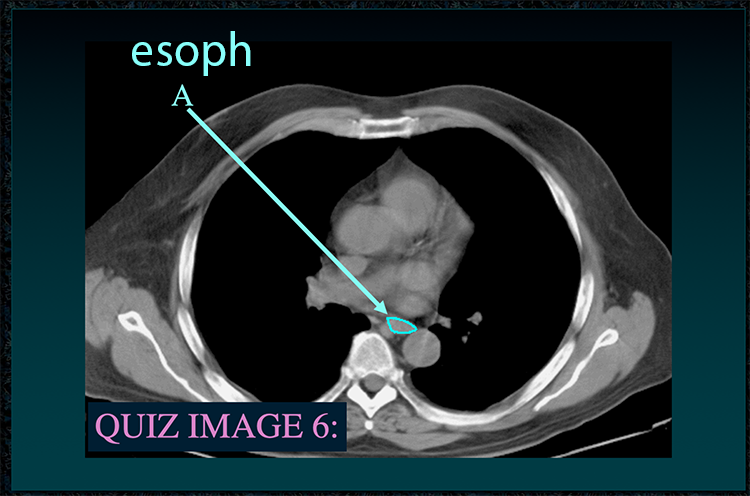

◂Chest Anatomy Review